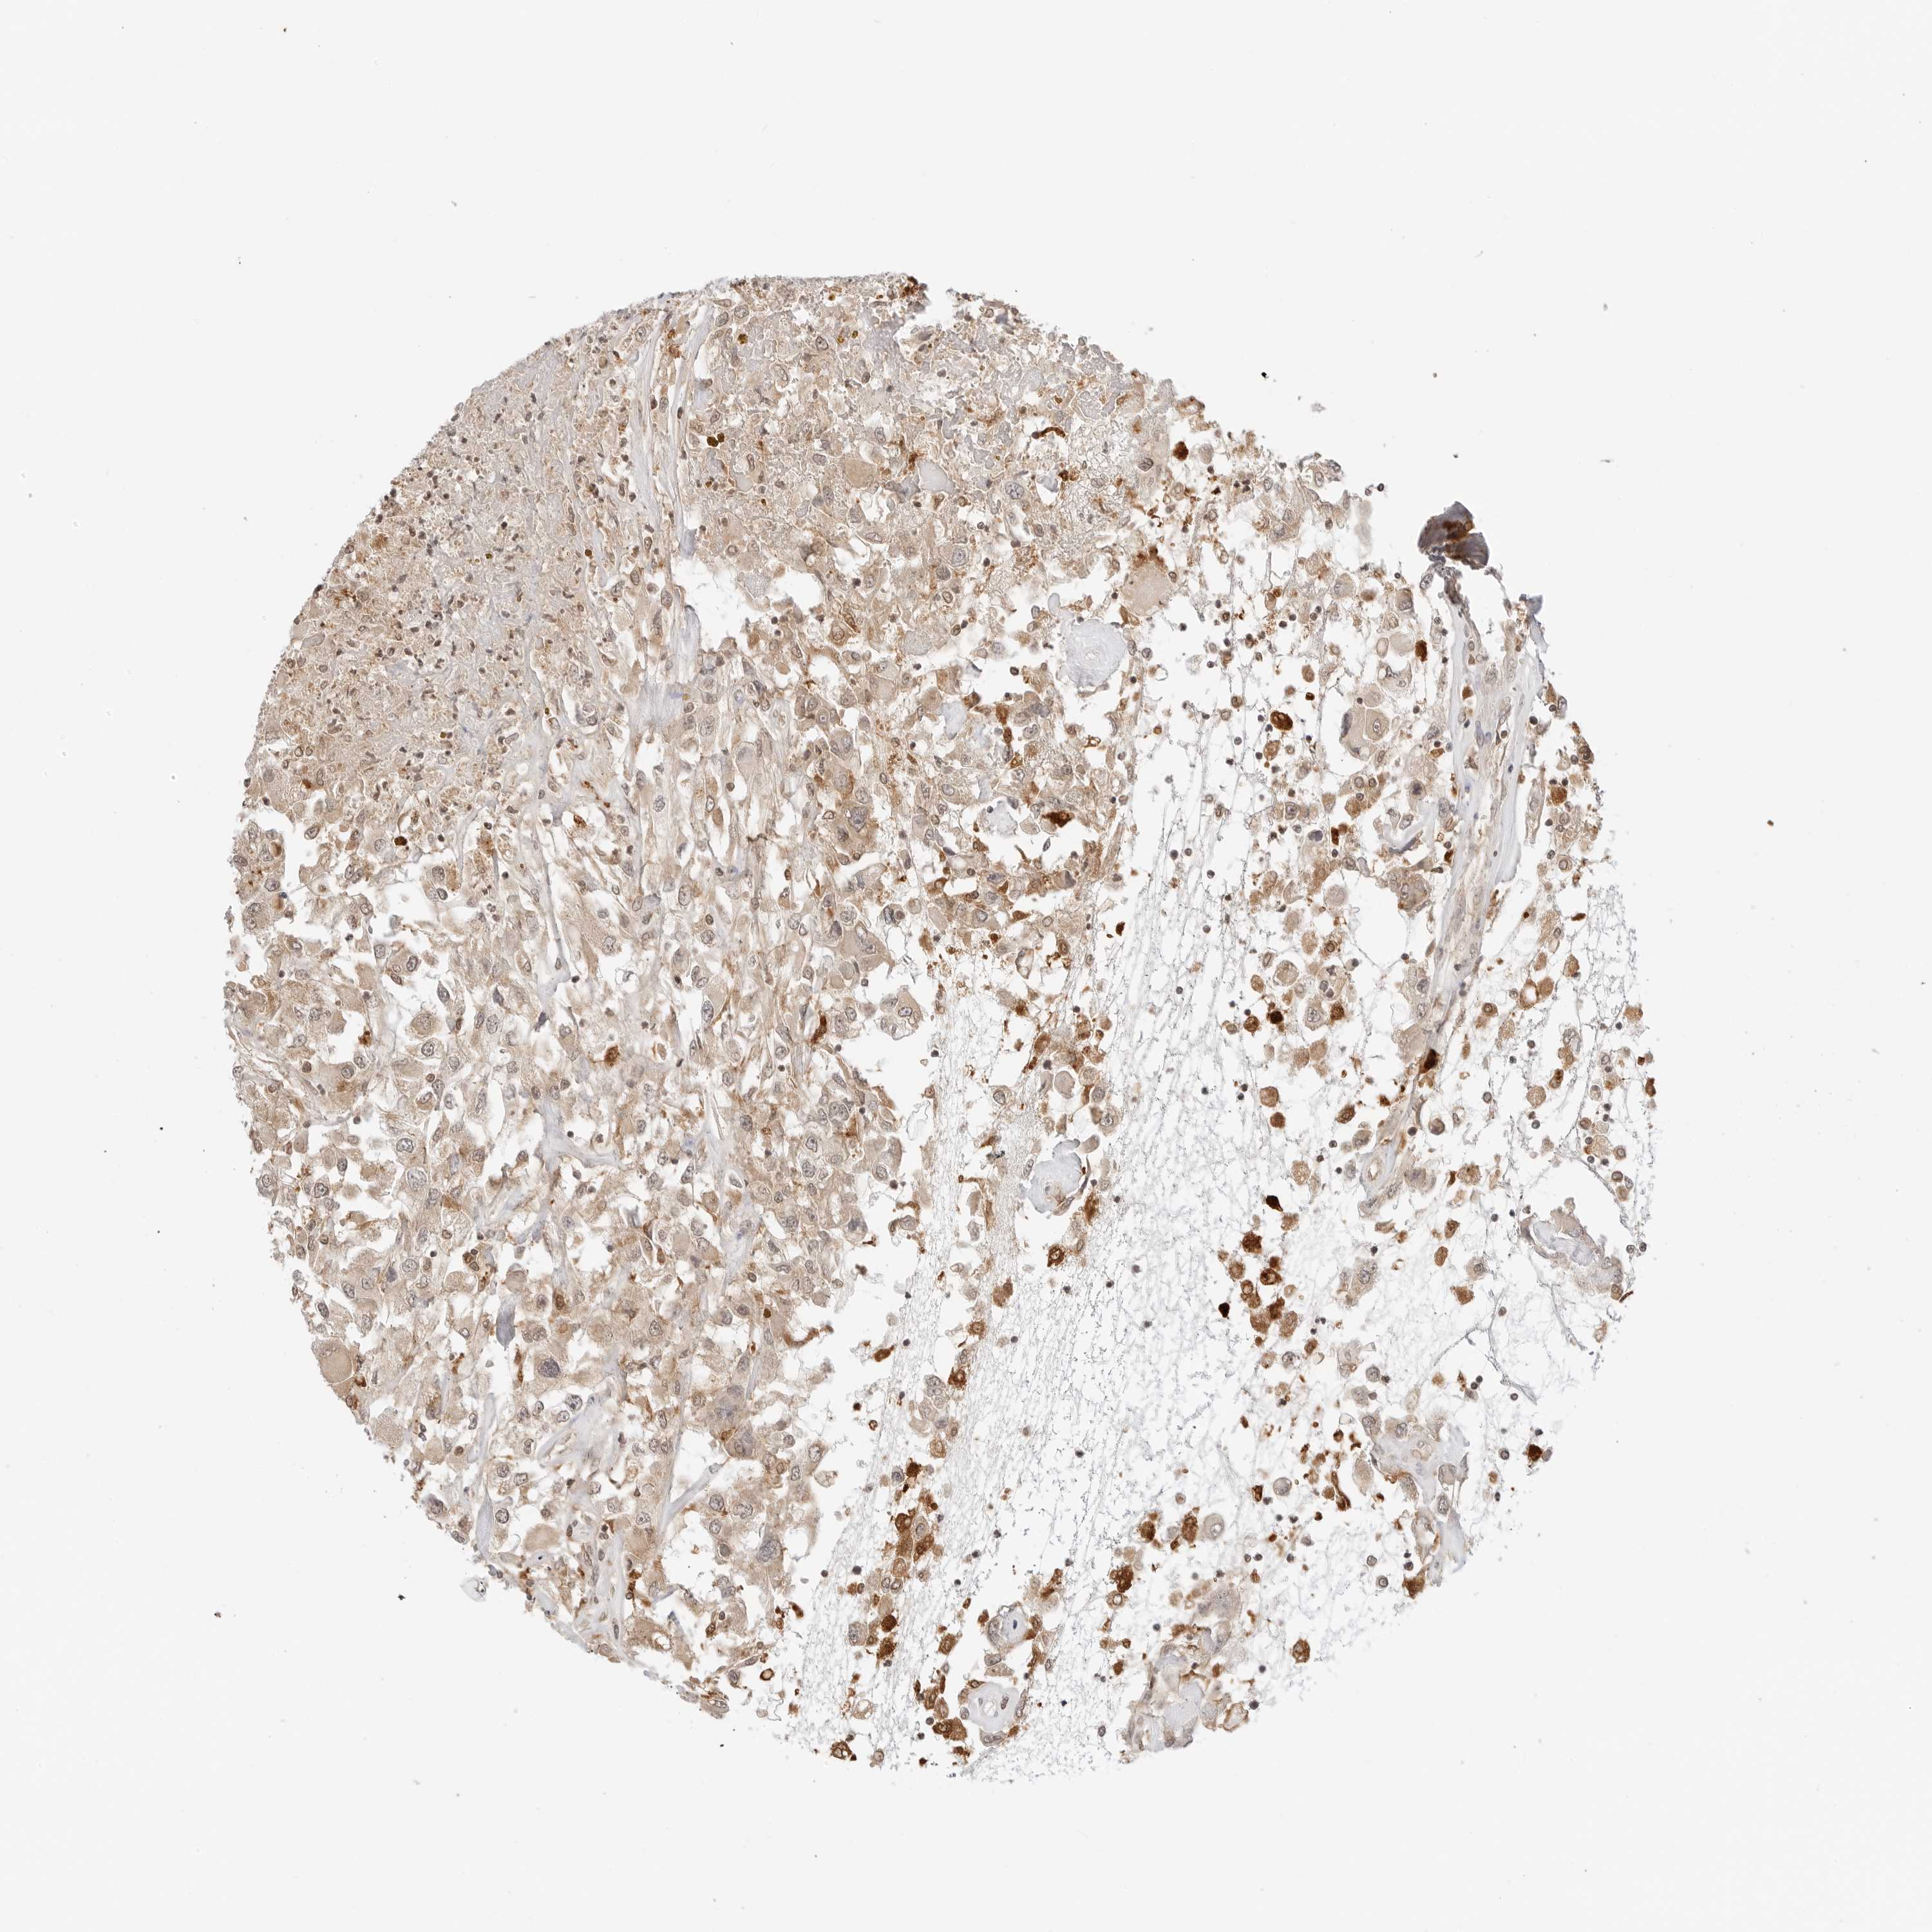

CANCER RENAL CANCER Show tissue menu